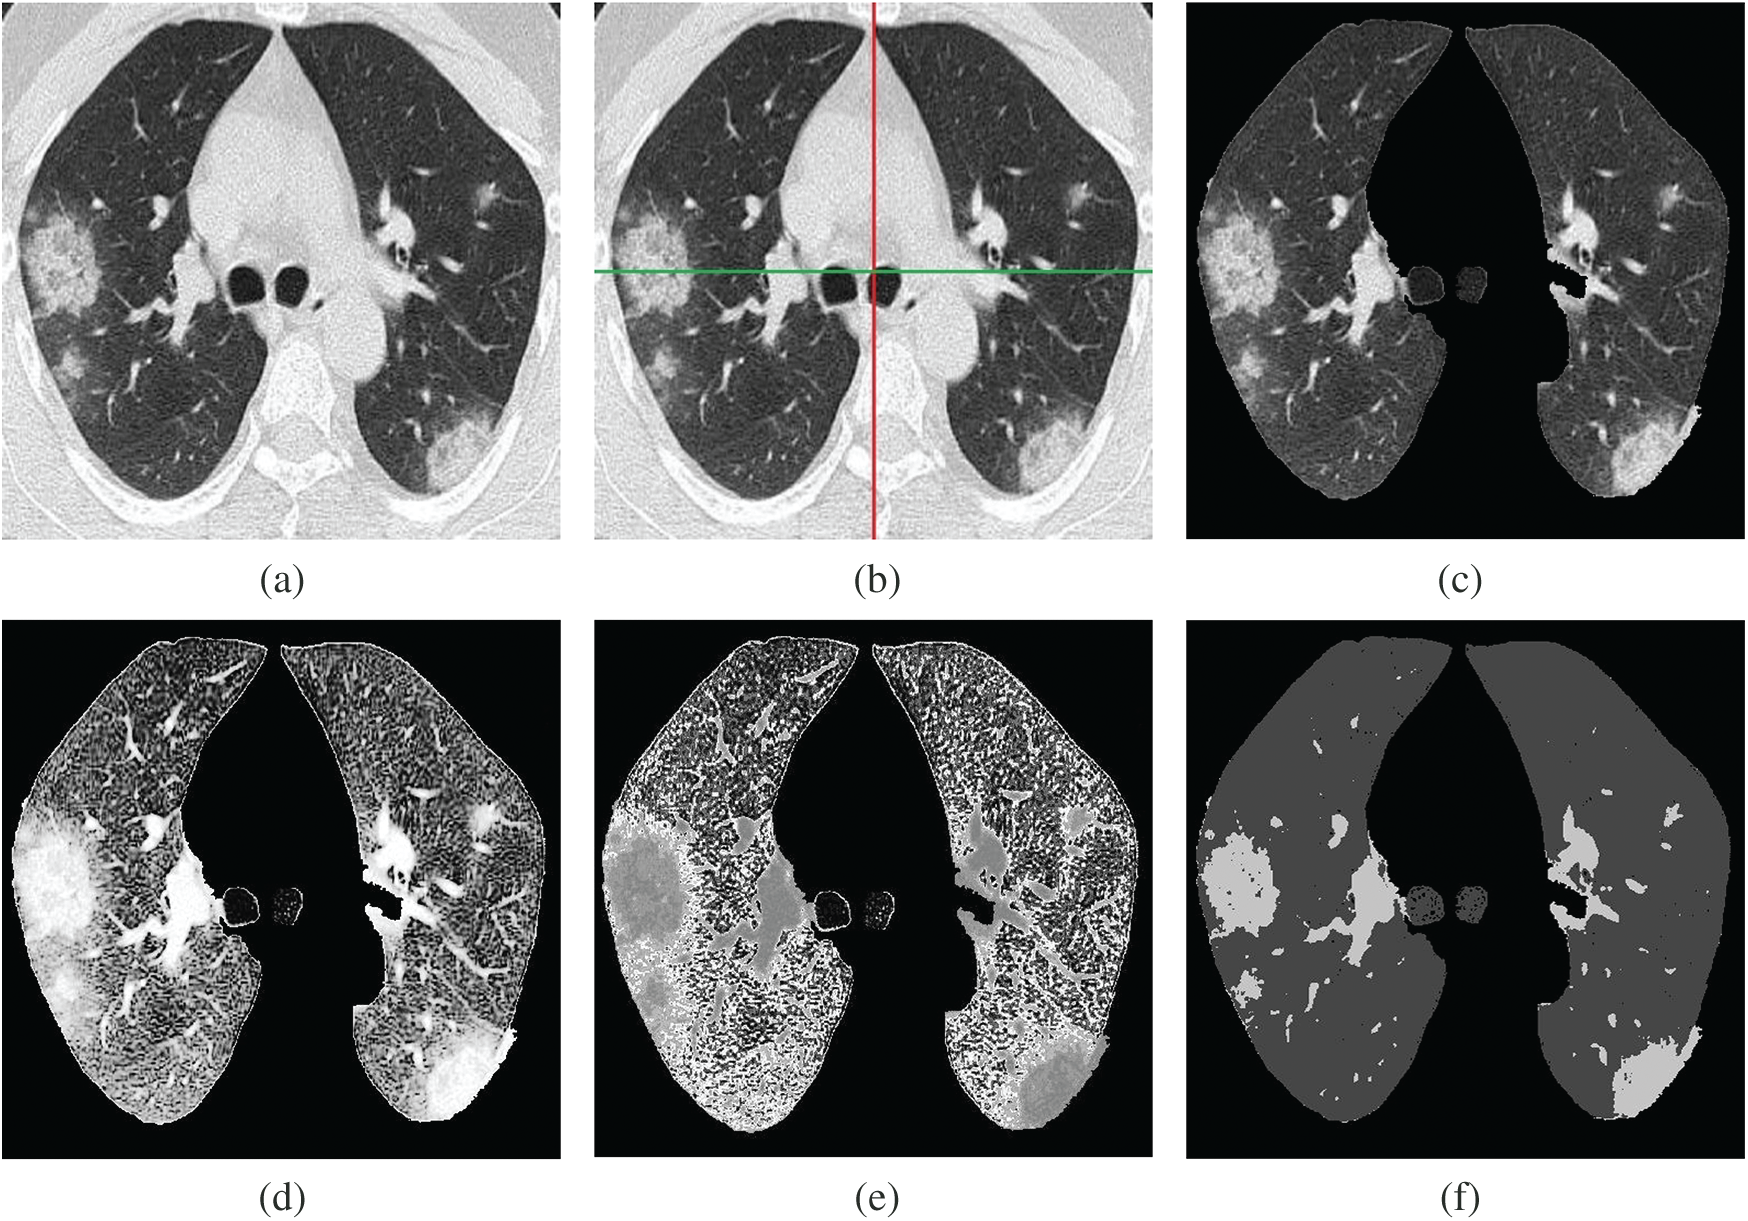

Figure 3: Fuzzy c-mean automated region-growing segmentation (FARGS) framework for COVID-19. (a) Lungs image (gray level), (b) Lungs image (segmented), (c) Lungs image (ROI extraction), (d) Lungs image (histogram stretch), (e) Lungs image (gray to natural binary), (f) Lungs image (fuzzy c-mean segmentation)